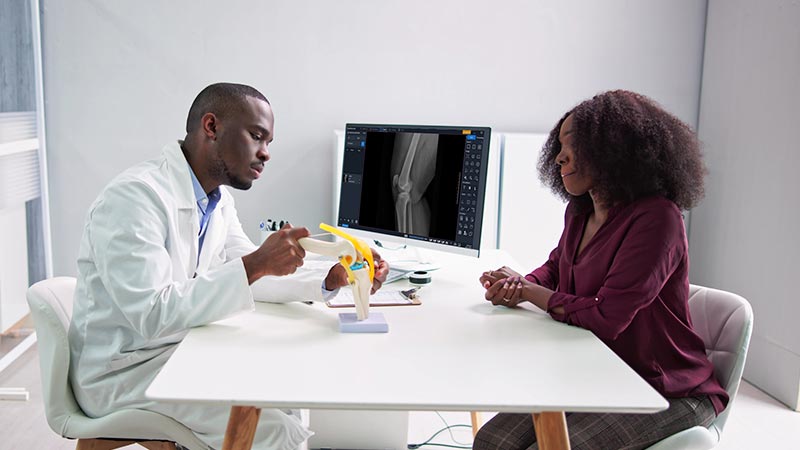

Cirugía y Ortopedia

Reduzca los tiempos de exposición de sus pacientes y sus profesionales con nuestros equipos precisos y de baja dosis.